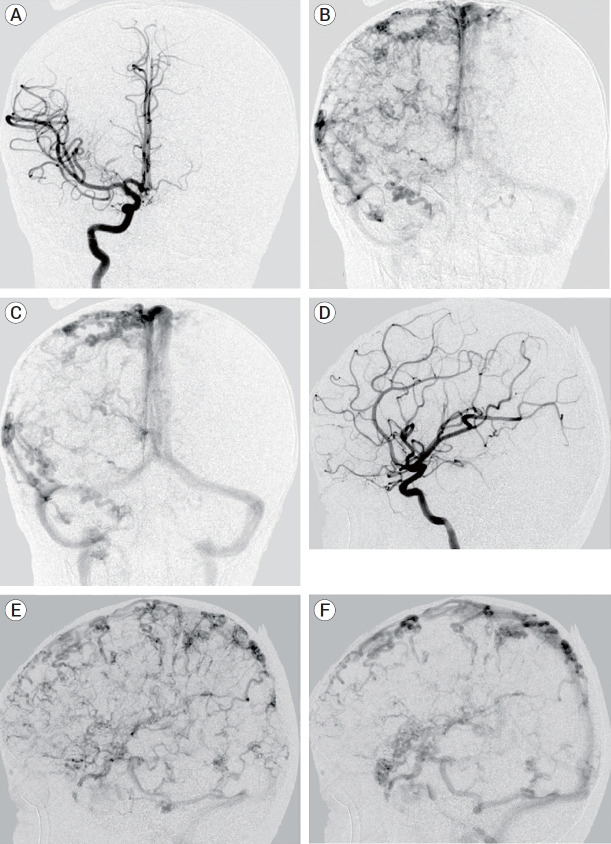

Partial trisomy of the long arm of chromosome 17 (17q) is a rare but clinically recognized syndrome that involves facial dysmorphisms, skeletal abnormalities, and global developmental delay, as well as various reports of cardiovascular, renal, and central nervous system abnormalities. This report presents a novel neuroradiologic finding of diffuse enlarged, tortuous cortical veins with physiological antegrade flow in a child with a microduplication of the distal end of 17q. To our knowledge, this finding has not been described previously. Although the exact cause for the cortical vascular anomaly is currently unknown, this duplicated region contains genes of interest for future studies that focus on normal and abnormal angiogenesis.